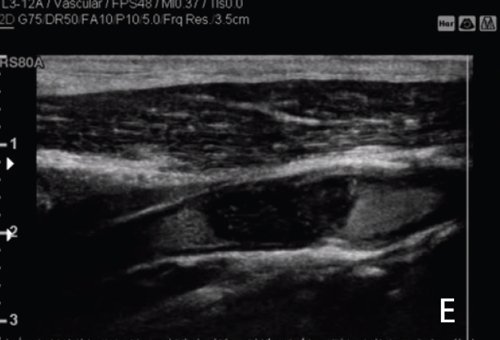

Рис. 5. При УЗИ в В-режиме (А) в постбульбарном отделе внутренней сонной артерии визуализируется гиперэхогенная гетерогенная неоднородная эхоструктура. Присутствие небольшой кальцинированной бляшки (белая стрелка), прилегающей к бульбарной стенке внутренней сонной артерии.

При цветовом допплеровском картировании (В) наблюдается слабый сигнал от сосуда по всему просвету сонной артерии. При транскраниальном цветовом допплеровском картировании (TCD) допплеровский спектр противоположной средней мозговой артерии (С) характеризуется низкой пиковой систолической скоростью и низкой систолически-диастолической модуляцией, особенно по сравнению с артерией на противоположной стороне (D).

УЗИ с контрастированием (E-F-G), выполненное с помощью высокочастотного линейного датчика, показывает равномерный просвет сонной артерии внутри луковицы. Отсутствие контрастного вещества подтверждено в постбульбарной части внутренней сонной артерии.

Окончательный диагноз: полная окклюзия постбульбарного отдела внутренней сонной артерии.